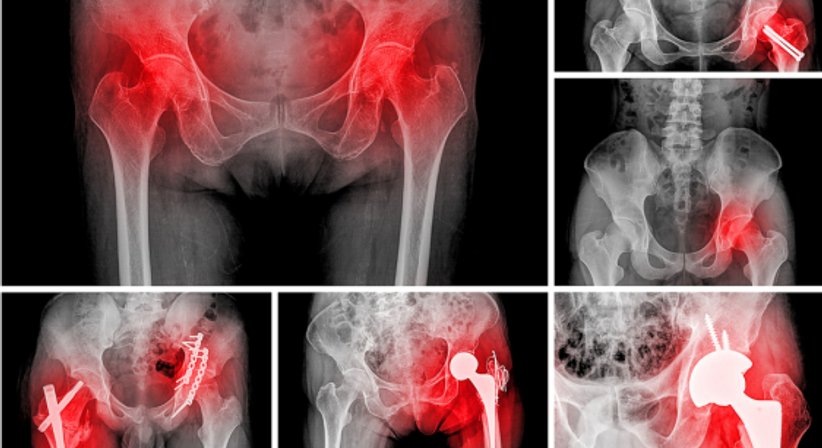

Hüftprothese

Eine Hüftprothese ersetzt ein geschädigtes Hüftgelenk. Neben Knieprothesen zählen Hüftprothesen zu den am häufigsten implantierten Prothesen im Bereich der orthopädischen Chirurgie, die häufigste Indikation für den Ersatz des Hüftgelenks ist die fortgeschrittene Hüftarthrose (Coxarthrose).

Nach dem Kniegelenk ist das Hüftgelenk das zweitgrößte Gelenk des menschlichen Körpers. Das Gelenk bildet den beweglichen Übergang zwischen dem Becken und dem Oberschenkelknochen. Schmerzen und Bewegungseinschränkungen im Bereich der Hüfte können auf verschiedene Ursachen zurückzuführen sein; ist das Hüftgelenk durch degenerative Veränderungen, Verletzungen oder Erkrankungen stark geschädigt bzw. verschlissen und helfen konservative und gelenkerhaltende Behandlungen (z.B. Physiotherapie, schmerz- und entzündungshemmende Medikamente) nicht mehr ausreichend, um die Schmerzen zu mildern und die Beweglichkeit und Funktionalität des Hüftgelenks in ausreichendem Maß wiederherzustellen, dann sollte über eine Hüftprothese ("künstliche Hüfte") nachgedacht werden, mithilfe welcher die Lebensqualität dauerhaft wiederherstellt werden kann.